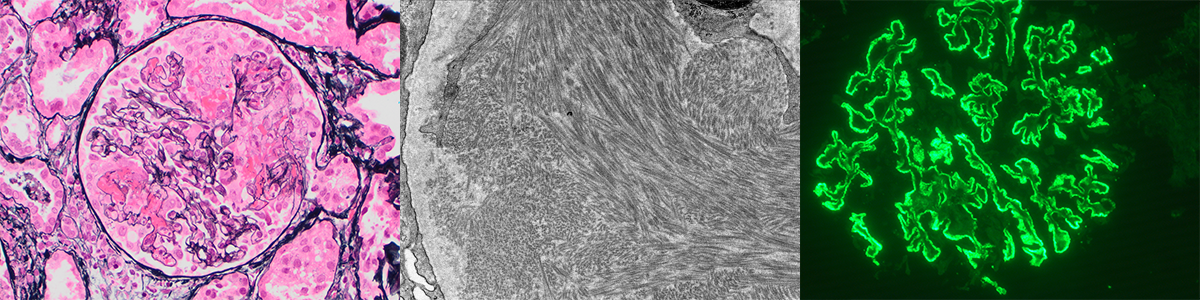

Renal microscope images

• Light microscopy (LM)

• Immunoflourescence Microscopy (IF)

• Electron Microscopy (EM)